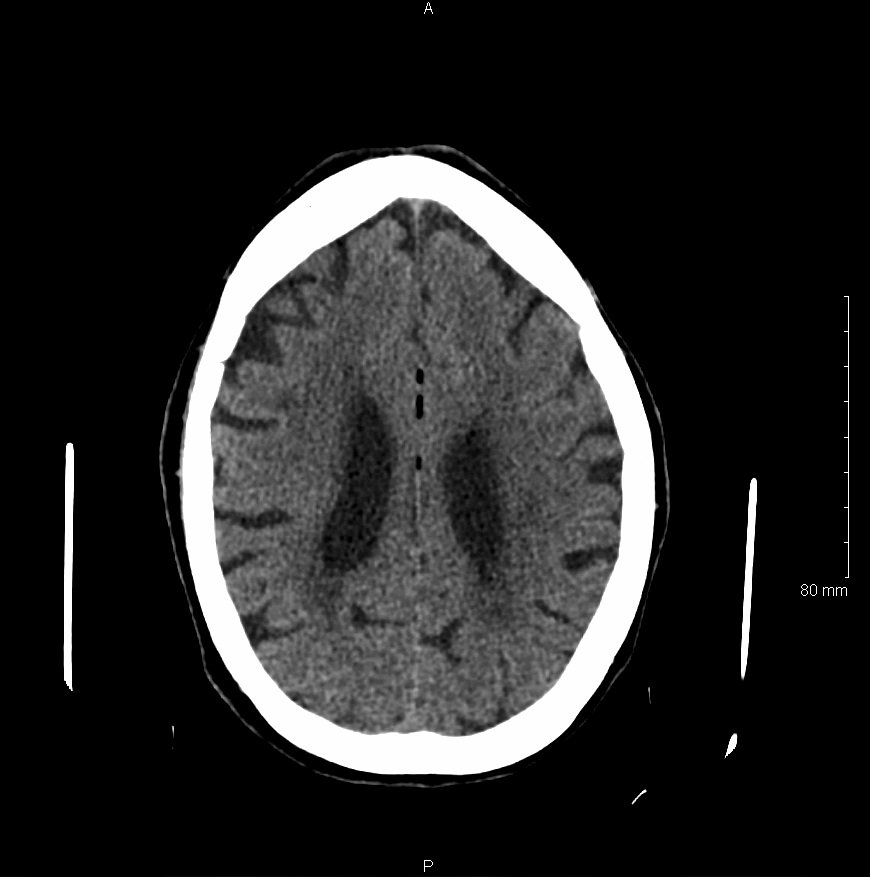

Non-contrast head computed tomography (CT) demonstrates multifocal bilateral hypodense lesions (white arrows) representing air emboli. Note the lesions are located in the intra-axial distribution which indicates an underlying vascular origin.

This event can arise in clinical and non-clinical settings and the diagnosis of cerebral air embolism should begin with clinical suspicion and evaluation. Most common causes include thoracentesis, hemodialysis, angiography, tissue biopsy, scuba diving, and central line or other vascular access procedures. Clinical signs of air embolism are broad depending on the affected system and include altered mental status, focal neurologic deficits in the distribution of the affected neurological region, cyanosis, hypoxia, hypercapnia, hypotension, wheezing, and bronchospasm.4 Recommended diagnostic imaging for cerebral air imaging includes CT and magnetic resonance imaging (MRI), but CT is most often performed first due to availability and the short duration of the test.5 The location of intracranial air emboli can be found in the intra-axial or extra-axial distribution and may indicate the possible etiology. Pneumocephalus is usually found in the extra-axial space most commonly after trauma or neurosurgery while air emboli are found in the intra-axial vascular distribution.6